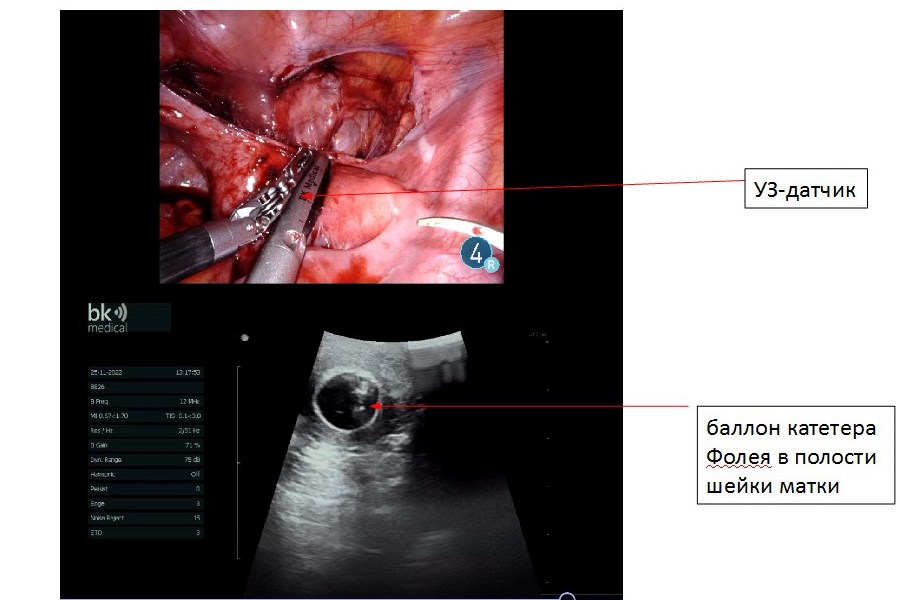

После предварительного этапа, во время которого пациентке проводили подготовку тканей промежности, психологическую поддержку, состоялась операция выполнения робот-ассистированного интроито-цервикального анастомоза, вследствие чего созданы условия для отведения менструальной крови в наиболее физиологическом варианте. Выполнению поставленной задачи способствовало применение интраоперационной эндоскопической ультразвуковой навигации. В операции попеременно участвовали шесть врачей-хирургов. Роботический этап операции выполнен М. С. Мосояном и Э. В. Комличенко. Ассистентами роботического этапа были врачи — В. А. Стасюкевич (гинеколог) и Д. А. Федоров (уролог), Н. А. Кохреидзе отвечала за навигацию, влагалищный этап, стратегирование, И. М. Каганцов — за навигацию и стратегирование. Следует отметить, что в мировой литературе описаны единичные случаи проведения таких операций.